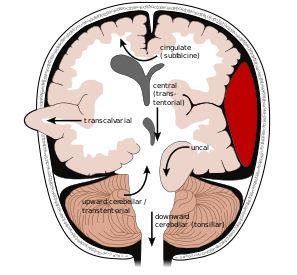

What are three different types of herniation that can occur in the brain when there is increased intracranial pressure?

- Subfalcine: cingulate gyrus pushed under the falx cerebri and herniated brain can become ischaemic due to compression of ACA that normally loops over corpus callosum and can get pinched

- Tentorial: medial temporal lobe (uncus) pushed through tentorial notch and can compress ipisilateral oculomotor nerve andipsilateral cerebral peduncle causing ipsilateral third nerve palsy but contralateral UMN signs in limbs.

Can be complicated by secondary brainstem haemorraghe (Duret Haemorraghe). Usual mode of death for those with large brain tumour and intracranial haemorraghe

Tonsillar: cerebella tonsils can be pushed in F.Magnum compressing the brainstem